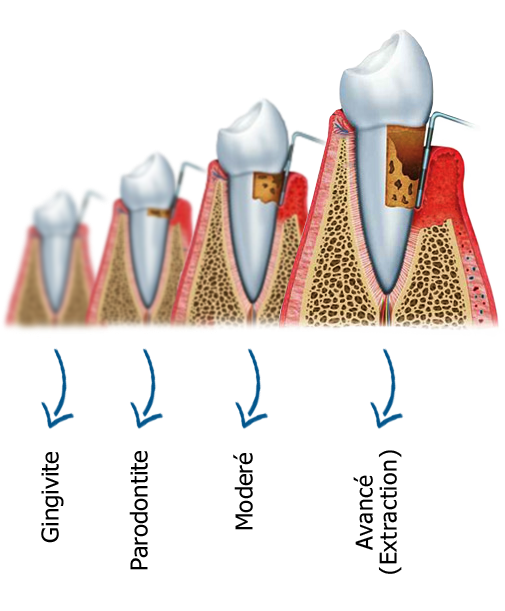

• La gingivite : L’infection atteint tout d’abord la gencive. Les signaux d’alerte sont des gonflements et des saignements de la gencive. Un brossage efficace permet généralement de stopper l’inflammation.

• La parodontite : Si la gingivite n’est pas traitée, l’inflammation continue son chemin, gagne l’os sous la gencive et provoque alors la destruction des tissus de soutien de la dent. Cette destruction se fait le plus souvent progressivement et imperceptiblement.

La parodontite conduit au déchaussement de la dent et favorise une mauvaise haleine (l’halitose). En l’absence de traitement, la parodontite s’étend pour provoquer les mêmes dégâts sur d’autres dents.